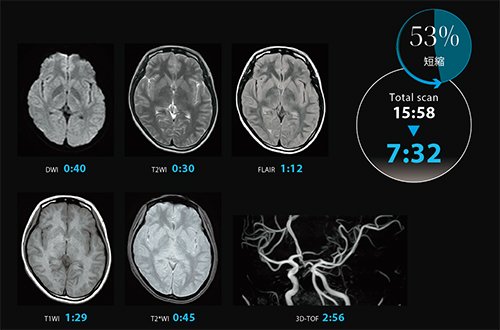

• Công cụ Clear-IQ thông minh tiên tiến (AiCE) tăng SNR giúp bạn nhìn xuyên qua tiếng ồn để mang lại hình ảnh rõ ràng, sắc nét và khác biệt trong thời gian quét phù hợp với lâm sàng

• SPEEDER nén giúp giảm thời gian quét trong khi vẫn duy trì hiệu suất chẩn đoán hình ảnh

• Một loạt các công nghệ quét nhanh bao gồm Fast 3D và Tách chất béo trong nước giúp giảm thời gian quét